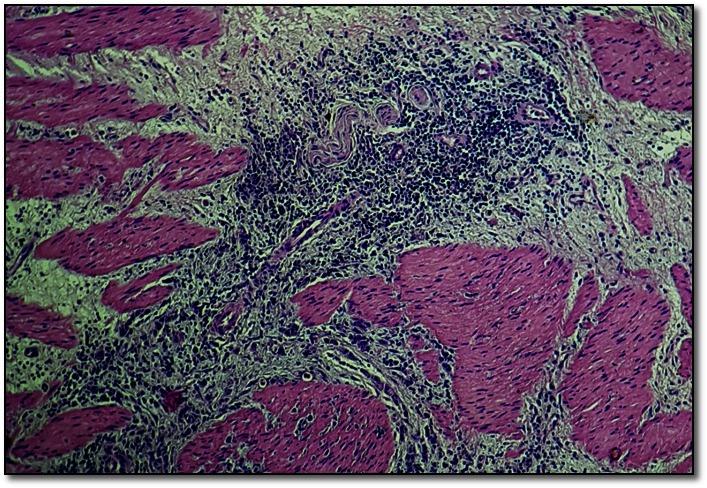

The paper presents the case of a male patient, hospitalized for acute abdomen due to perforated callous ulcer. Though the clinical appearance suggested a benign pathology, the histopathological exam of the resection piece showed multicentric early gastric carcinoma, signet ring cell type. At the patient's request, total gastrectomy was not performed, a conservative solution being chosen instead. Superior digestive endoscopy with biopsy and oncological dispensarization was performed one month after surgery, then at every 6 months. After 2 years of benign results, the histopathological exam revealed the presence of malign singlet ring cells in the bioptic specimen. Respecting the patient's option of preserving a good quality of life, subtotal gastrectomy with Pean type gastroenteroanastomosis was performed followed by postoperatory chemotherapy. Endoscopic and oncological follow-up were performed at every six months for another 3 years (up to present), and the evolution was favorable with no local or metastatic recurrence. Histopathological examination was of great help in the surgical management of this case, allowing a fortunate early diagnosis, a conservative surgical approach, and the preserving of a good quality of life.

本文介绍了一名男性患者的病例,该患者因胼胝性溃疡穿孔导致急腹症而住院。尽管临床表现提示为良性病变,但切除组织的组织病理学检查显示为多中心早期胃癌,印戒细胞型。应患者要求,未进行全胃切除术,而是选择了保守治疗方案。术后1个月进行了上消化道内镜检查及活检和肿瘤专科诊疗,之后每6个月进行一次。在2年的良性结果后,组织病理学检查显示活检标本中存在恶性印戒细胞。考虑到患者保留良好生活质量的选择,进行了Pean式胃肠吻合术的胃次全切除术,随后进行术后化疗。此后每6个月进行一次内镜和肿瘤学随访,持续3年(直至目前),病情进展良好,无局部或转移复发。组织病理学检查对该病例的手术管理有很大帮助,使得能够幸运地早期诊断、采取保守手术方法并保留良好的生活质量。